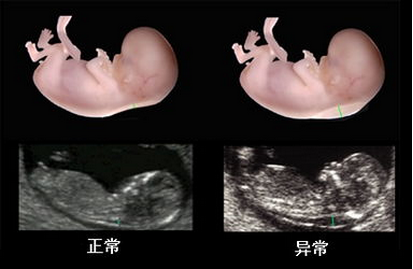

在线咨询系统彩超是孕妈妈非常重要的一项检查, 可以指导优生优育,通过系统检测胎儿生长发育情况。在检查时孕妈妈一定要把握好做系统彩超的黄金时间,那么怀孕多久做系统彩超比较合适呢?

孕早期的系统彩超检查的黄金时间为孕11-14周,这个时候可以通过颈后透明层排除宝宝先天愚型和智力缺陷,而孕晚期系统彩超黄金时间是30--34周,可以对胎儿进行全身系统检查,但具体的检查时间,还是应该根据孕妈妈自身情况来决定,同时,孕妈妈要注意选择一家专业的医院进行系统彩超,才能够达到预期的检查效果。

在检查过程中医生会仔细的对脊椎、头颅、内部、腹部等身体内部各器官进行逐一检查,全面的排查可能存在的异常。